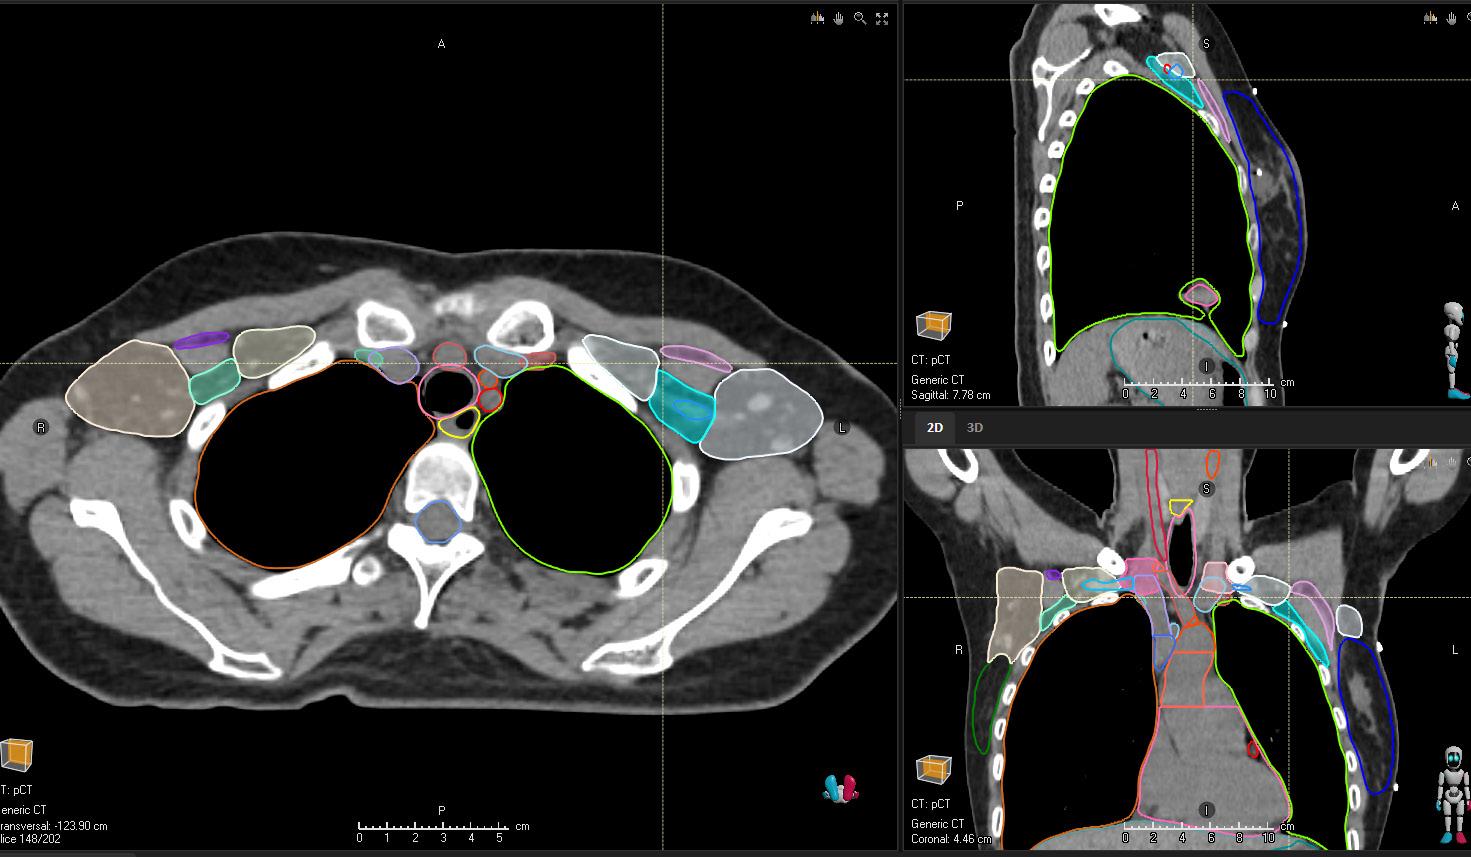

Deep learning capabilities in RayStation®* help make image segmentation quicker and more consistent. A high-speed GPUpowered algorithm is capable of producing consistent segmentation results using guideline-based segmentation models that have been trained and evaluated on curated data for different body sites.

BREAST CT

STRUCTURES

Breast_L

Breast_R

LN_Ax_L1_L IMPROVED

LN_Ax_L1_R IMPROVED

LN_Ax_L2_L IMPROVED

LN_Ax_L2_R IMPROVED

LN_Ax_L3_L IMPROVED

LN_Ax_L3_R IMPROVED

LN_Ax_Pectoral_L IMPROVED

LN_Ax_Pectoral_R IMPROVED

LN_IMN_L

LN_IMN_R

LN_L4_L IMPROVED

LN_L4_R IMPROVED

HEART SUBSTRUCTURES

A_Aorta_Asc_Prox NEW

A_Aorta_Root NEW

A_LAD

A_Pulmonary NEW

Atrium_L NEW

Atrium_R NEW

V_Pulmonary NEW

V_Venacava_S_Prox NEW

Ventricle_L NEW

Ventricle_R NEW